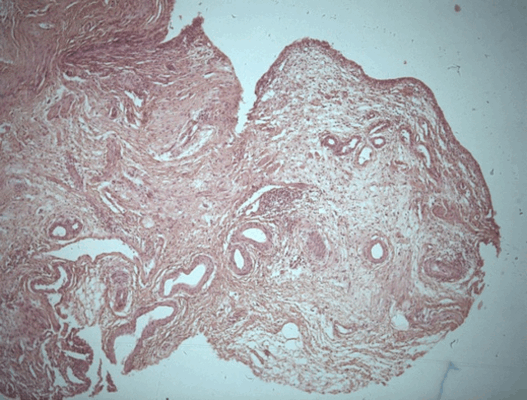

Патоморфологическое исследование пациента М.

Морфологическая картина полипоидного цистита. Окраска гематоксилин-эозином, х5

Патоморфологическое исследование пациента С.